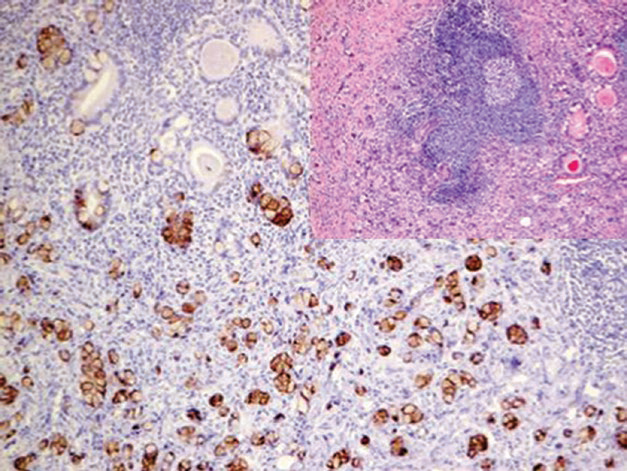

It should be noted that EMA is not a specific epithelial marker and can be widely expressed in non-epithelial tumors and cell types, such as anaplastic large cell lymphoma, plasma cell tumors, meningioma, epithelioid mesothelioma, perineurioma, synovial sarcoma, epithelioid sarcoma, and neurogenic sarcoma. EMA expression is also commonly seen in nodular lymphocyte-predominant Hodgkin lymphoma.

Figure 1. (Left) Positive EMA expression in atypical meningioma; (Right) Focal positive EMA expression in neurogenic sarcoma.

Positive expression pattern: Cell membrane or cytoplasm.

Recommended positive control tissues: Appendix, tonsil.